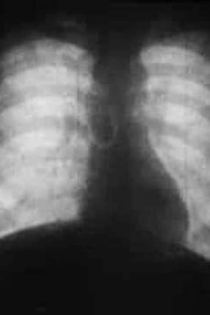

This silent b&w film has intertitles in gothic script (in German). The film features cineradiography of x-rays of the chest shot full-on and side-on. The sequences are listed (in English) on the box on the negative copy 'Respiration (undecipherable)' and 'Deep Child frontal and lateral views', 'Adult frontal and lateral views' 'Adult diaphragm'.